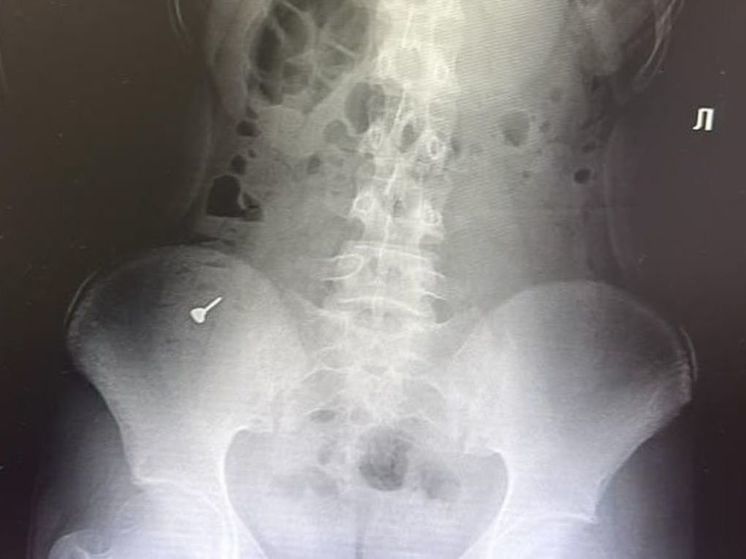

Раменские врачи удалили из кишечника 17-летней пациентки деталь от пирсинга. Девушка случайно проглотила украшение и пожаловалась на боли в животе, сообщает пресс-служба Минздрава Подмосковья.

В Раменскую больницу в сопровождении родителей поступила 17-летняя пациентка. Девушка проглотила деталь от пирсинга и жаловалась на сильные боли в животе. Диагностика показала наличие 3-сантиметрового металлического предмета, застрявшего в области слепой кишки.

По словам медиков, инородный предмет, попавший в кишечник, представляет серьезную опасность для здоровья. Он способствует перфорации стенки органа. Через образовавшееся отверстие деталь может провалиться в брюшную полость и вызвать непоправимые последствия. Поэтому врачи приступили к экстренной операции. Инородное тело извлекли эндоскопическим путем. Врачи выполнили колоноскопию и достали пирсинг. Девушка идет на поправку и уже выписана из больницы. А специалисты советуют в случае проглатывания инородного предмета незамедлительно обращаться за медицинской помощью.